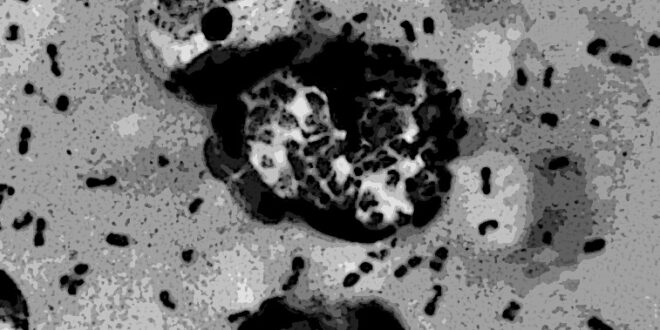

NUEVA YORK. Un caso de peste bubónica en humanos ha sido detectado en Estados Unidos, concretamente en el estado de Oregon. El contagio se habría producido a través de un gato doméstico, tal y como...